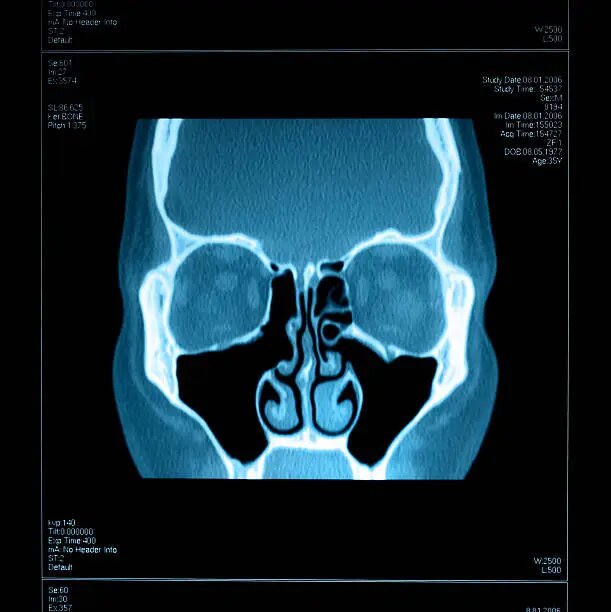

Исследование МРТ было создано для изучения мягкотканых образований: головного мозга, органов желудочно-кишечного тракта, печени, лёгких. При проведении МРТ на уровне черепа можно визуализировать глазные яблоки, потому что это тоже мягкотканые образования. Околоносовые пазухи тоже попадают под прицел, но из-за наличия в воспалённой пазухе жидкости, сигнал не жёсткий. Заметная будет только грубая патология. Она же будет видна и на рентгеновском снимке. Но если нам нужно чётко визуализировать патологическую картину на фоне костных и хрящевых контуров, справиться с этой задачей сможет только компьютерная томограмма.

Благодаря КТ лор-врач может ясно определить уровень жидкости, предположить её характер (что находится в пазухе: прозрачное содержимое или гнойные выделения), выявить мукоцеле в лобной пазухе, определить кистозную или полипозную ткань. Полип – это целостная структура. Он как виноградина: если полип разрезать пополам, внутри будет мякоть. Киста всегда будет шаровидной формы. Она напоминает воздушный шар, который наполнили водой. Это тончайшая оболочка, которая заполнена кистозной жидкостью. КТ также поможет врачу определить, откуда произрастает киста или полип.